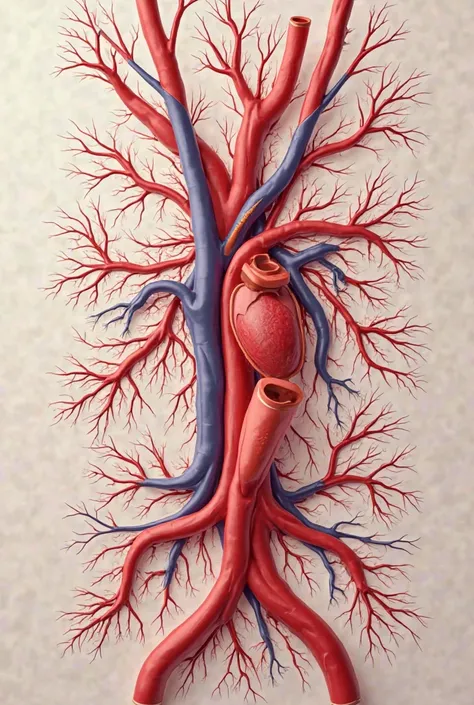

Realice un dibujo de la piel. Coloque las siguientes referencias: Epidermis Fermis Hypodermis Keratinized squamous stratified epithelium Hair Sebaceous gland Sweat gland Pilo erector muscle Connective tissue Blood vessels Nerves Adipocytes

Epidermis Fermis Hypodermis Keratinized squamous stratified epithelium Hair Sebaceous gland Sweat gland Pilo erector muscle Connective tissue Blood vessels Nerves Adipocytes